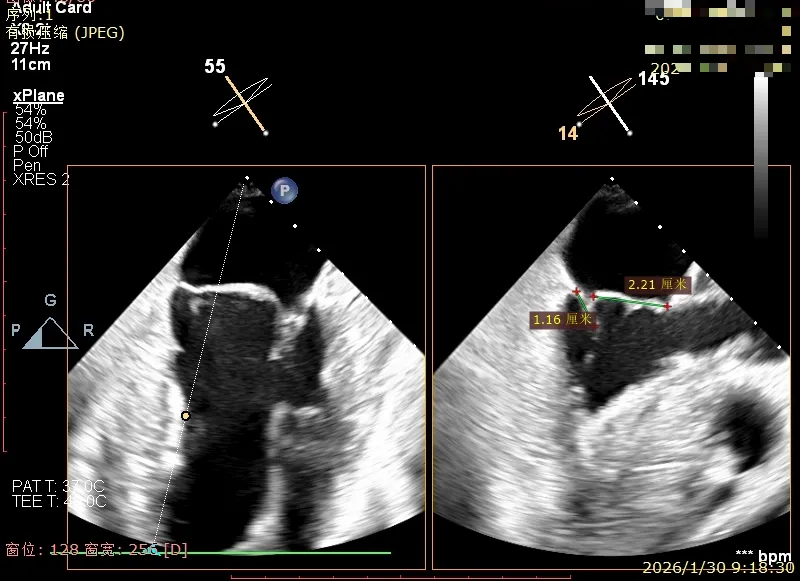

经食道超声精细化测量:肺静脉逆流,房间隔可穿刺高度约4.2cm,Flail宽度约21mm,Flail高度约8mm,Flail Gap约4mm, 3区AML长约23mm、PML长约12mm、2区AML约32.2mm,PML约16mm。

2区前叶长度约32.2mm,后叶长度约16mm

2区Flail Gap约4mm